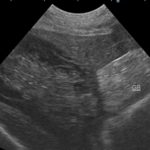

胆嚢摘出 黄疸が進行し、超音波検査で胆嚢粘液嚢腫と診断されたわんこの手術をして欲しいと連絡がありました。十二指腸を切開し総胆管を洗浄、胆嚢摘出を行いました。術後は十二指腸カテーテルを挿入し栄養管理を行います。 症例カテゴリー 放射線治療整形外科軟部組織外科脳神経外科内科腫瘍外科救急・集中治療リハビリテーション科腫瘍内科内視鏡科脳神経科呼吸器外科中医・漢方猫の腎移植循環器科